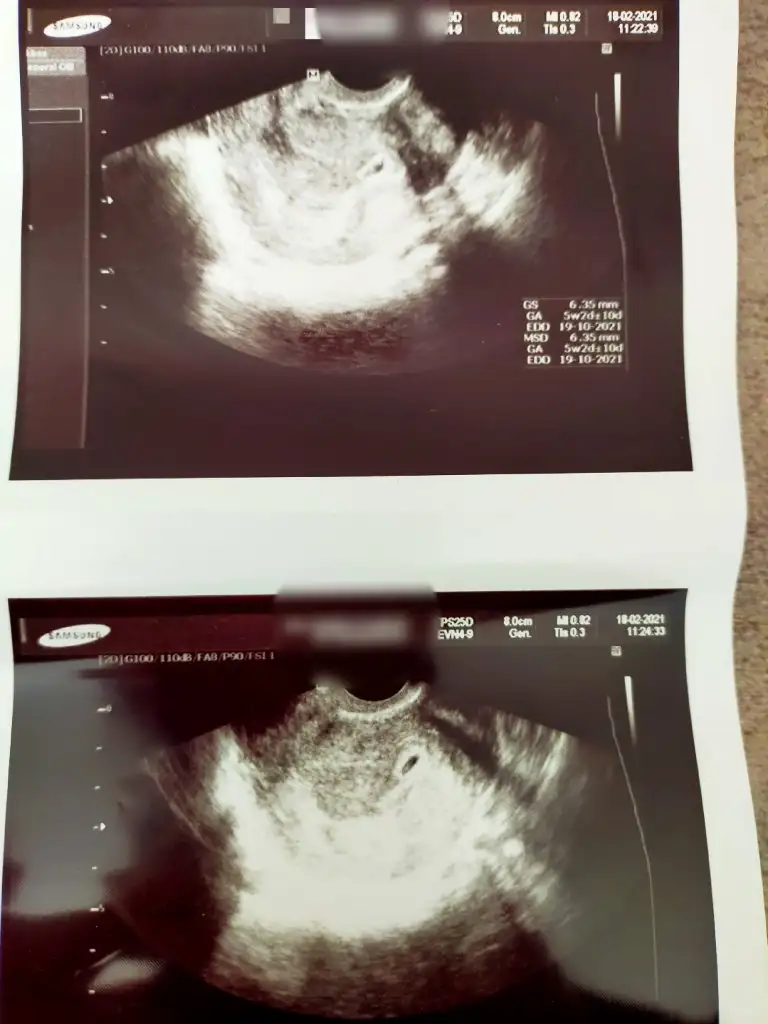

Sat 01 Ocak ona göre 7+0 olmaliydi bugun dünkü kese fotosunu da önceki günüde atayım bı fark varmı bakBetanın önemi yok derken, kese göründükten sonra o takip edilir demek oluyor. 5+2 ultrasonda olan. Pekii adetine göre dün kaç olması gerekiyordu canım?

Vajinalmi bakildi kese ?Sat 01 Ocak ona göre 7+0 olmaliydi bugun dünkü kese fotosunu da önceki günüde atayım bı fark varmı bak

Evet canım vajinalVajinalmi bakildi kese ?